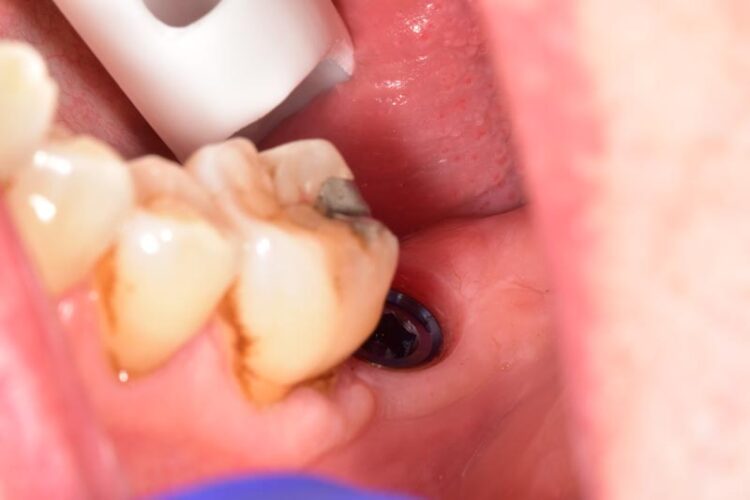

After three months the healing abutment was then removed. The presence of the healing abutment facilitated the development of an emergence profile from the implant platform during the healing phase. A fixture level impression was taken and a screw-retained crown with the screw emerging in the mid-occlusal area was fabricated. The crown was made on a zirconia framework on a hybrid base abutment layered with e.max ceramic with ultra-polished zirconia subgingivally.

This case beautifully demonstrates the emergence profile that the tissue level implants facilitate along with the ease of cleansability for the patient, even when the prosthesis is placed posteriorly in difficult to reach areas.